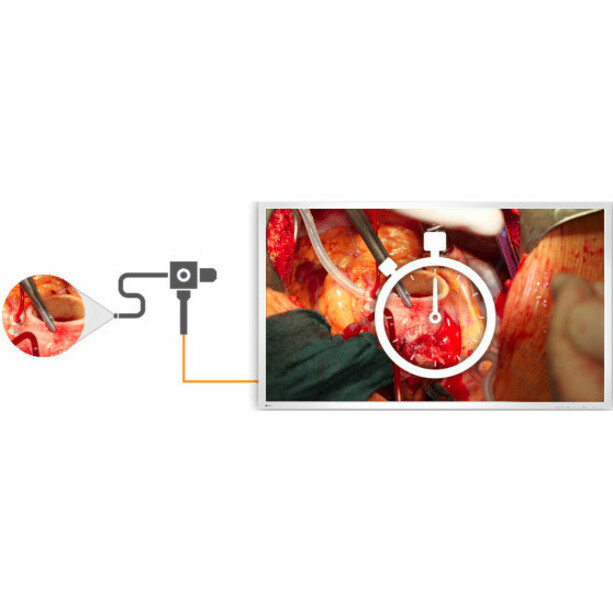

Delay-Free Display of Images

In single source mode, 4K images, as well as full HD images shot by conventional endoscopy and surgical cameras can be displayed in high definition without any delay, making full use of the monitor's 4K UHD resolution.